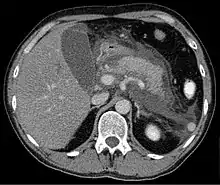

Axial CT in a patient with acute exudative pancreatitis showing extensive fluid collections surrounding the pancreas

Regarding the need for computed tomography, practice guidelines state:

CT is an important common initial assessment tool for acute pancreatitis. Imaging is indicated during the initial presentation if:

CT findings can be classified into the following categories for easy recall:

• Intrapancreatic – diffuse or segmental enlargement, edema, gas bubbles, pancreatic pseudocysts and phlegmons/abscesses (which present 4 to 6 wks after initial onset)

• Peripancreatic / extrapancreatic – irregular pancreatic outline, obliterated peripancreatic fat, retroperitoneal edema, fluid in the lessar sac, fluid in the left anterior pararenal space

• Locoregional – Gerota's fascia sign (thickening of inflamed Gerota's fascia, which becomes visible), pancreatic ascites, pleural effusion (seen on basal cuts of the pleural cavity), adynamic ileus, etc.

The principal value of CT imaging to the treating clinician is the capacity to identify devitalised areas of the pancreas which have become necrotic due to ischaemia. Pancreatic necrosis can be reliably identified by intravenous contrast-enhanced CT imaging,[20] and is of value if infection occurs and surgical or percutaneous debridement is indicated.